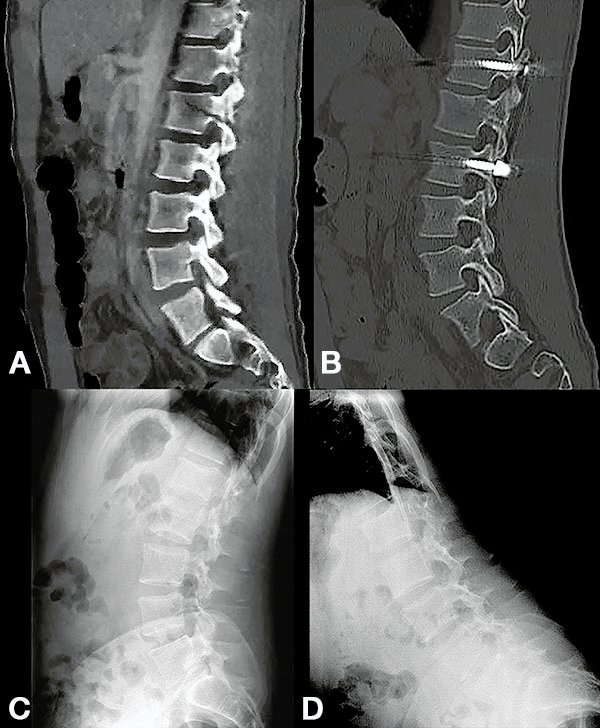

Figura 3:

Caso 24. A: Fractura L1: B1; N1. B: Control 7 meses que evidencia consolidación. C y D: Retiro de osteosíntesis a los 9 meses con buena movilidad en las radiografías dinámicas de control.

Figura 6:

Caso 8. A la semana de la primer cirugía el paciente se encontraba en condiciones y se realizó la corpectomía por via lateral MIS.

Figura 7:

Caso 8. Control postoperatorio alejado del paciente con un buen callo de fusión, sin pérdida de corrección.